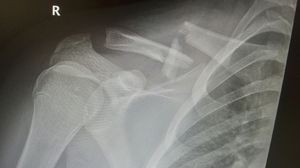

Xray

Claviclefracture